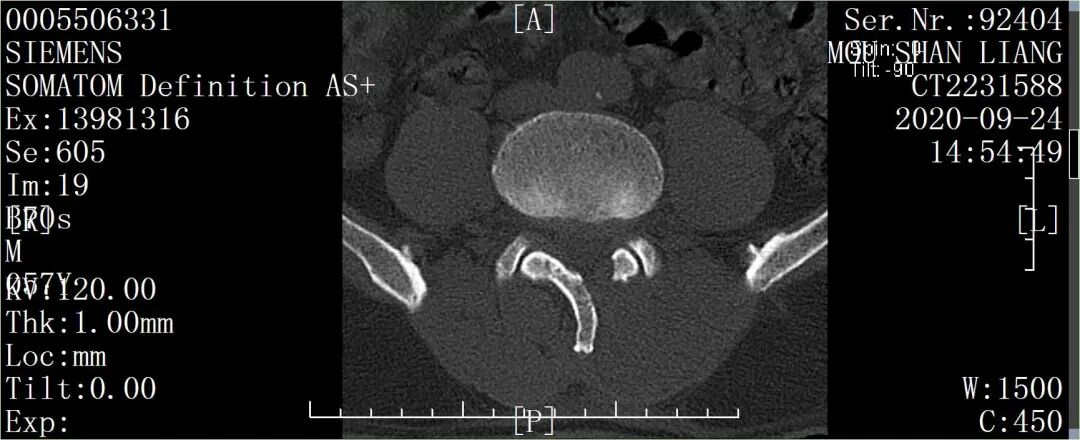

图7:术后影像

图8:术后影像

图9:术后影像